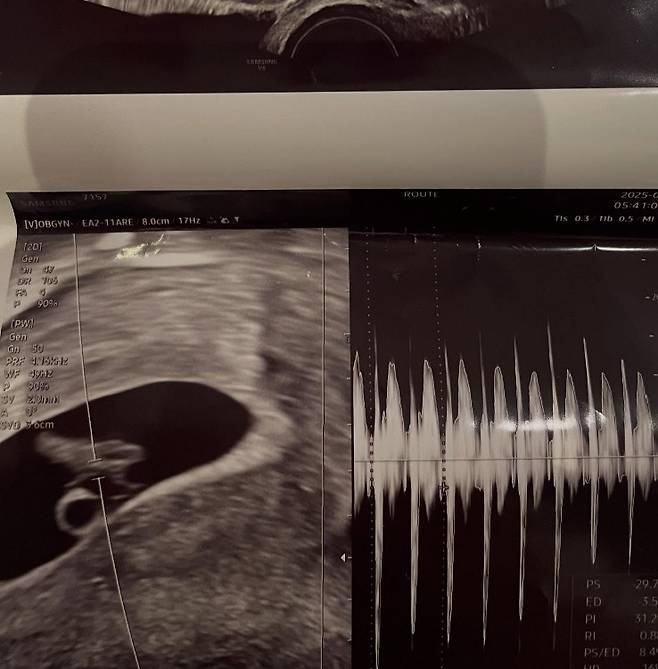

2일 서민재는 개인 계정에 "아빠 된 거 축하해"라는 글과 함께 임신 소식을 알렸다.

사진에는 서민재의 것으로 추정되는 초음파와 함께, 남자친구와 다정하게 붙어 셀카를 찍고 있는 모습이 담겼다.